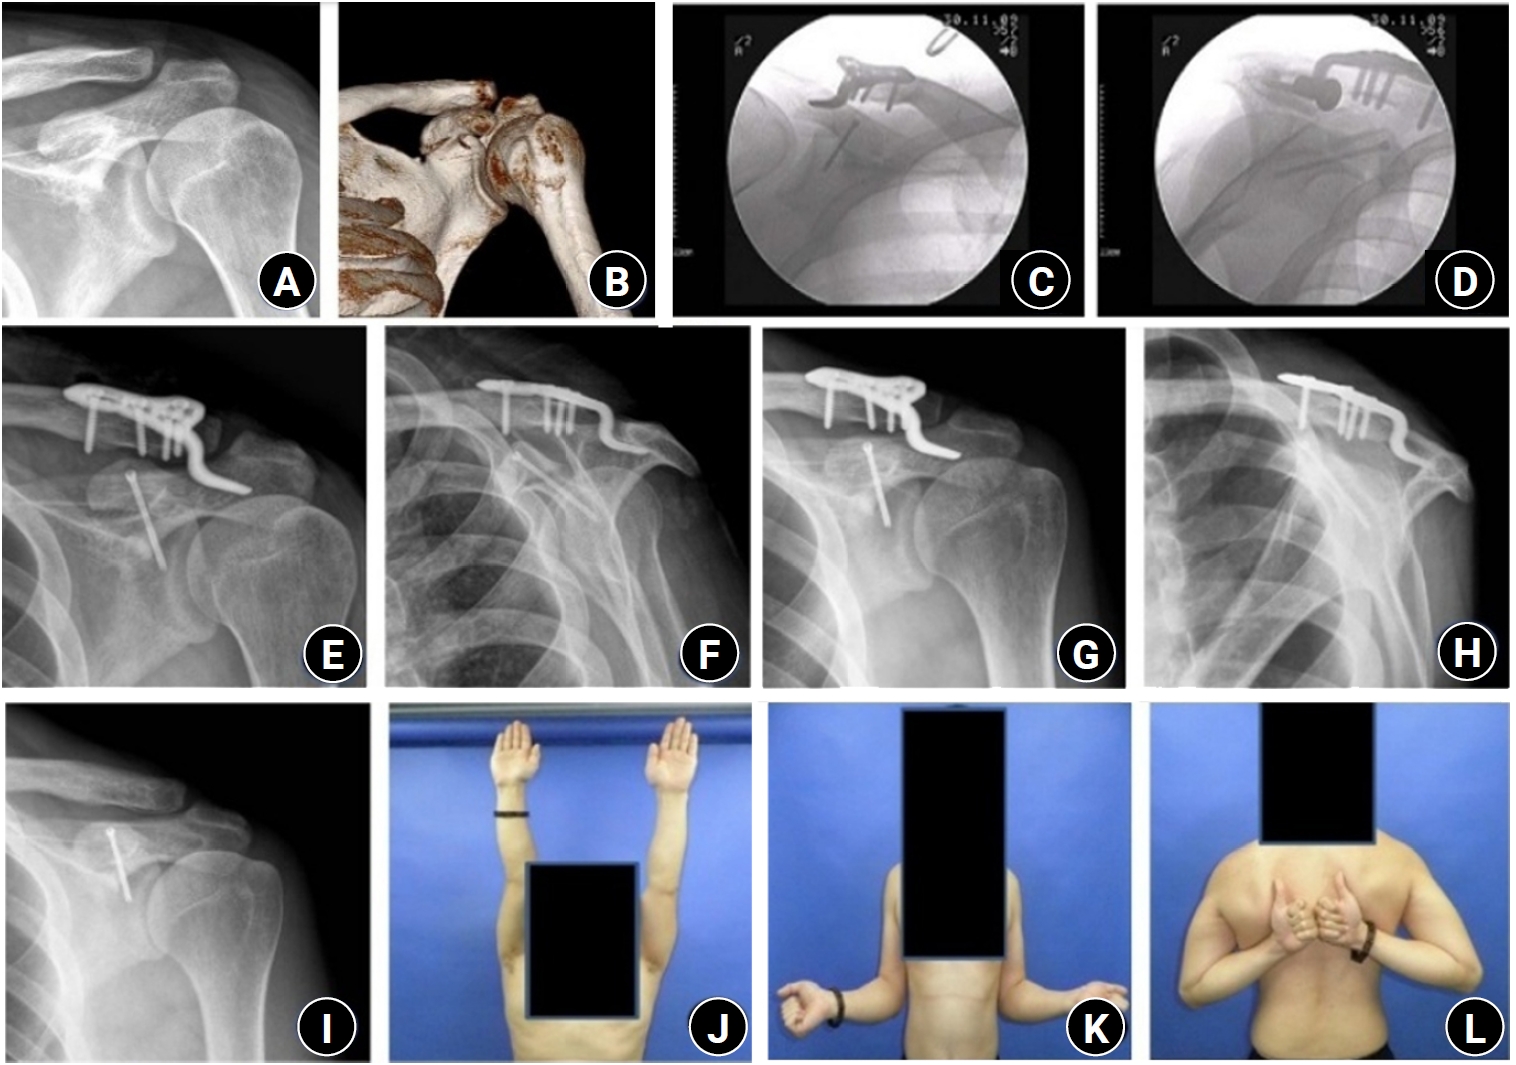

Postoperative complications and implant removal

No postoperative infections or neurovascular complications were observed in any of the patients. However, one patient experienced nonunion. The K-wire for ACJ fixation was removed at 6 weeks after the operation, and nonunion of the coracoid fixation was confirmed at the final follow-up of 6 months, but the patient's clinical outcome was good (Fig. 2).

Fig. 2.

Three-dimensional computed tomography (A) and shoulder anteroposterior (AP) radiograph (B) of a 74-year-old male patient show a coracoid process fracture associated with an acromioclavicular joint (ACJ) injury. (C) A 3.0-mm headless compression screw was used for the coracoid process fracture, and two Kirschner (K)-wires were used for the ACJ injury. (D) Postoperative 2-week radiographs show K-wire deformation. (E) Postoperative 6-week radiographs show K-wire loosening. (F) Postoperative 6-month AP radiographs show nonunion of the coracoid process.

Fig. 2. Three-dimensional computed tomography (A) and shoulder anteroposterior (AP) radiograph (B) of a 74-year-old male patient show a coracoid process fracture associated with an acromioclavicular joint (ACJ) injury. (C) A 3.0-mm headless compression screw was used for the coracoid process fracture, and two Kirschner (K)-wires were used for the ACJ injury. (D) Postoperative 2-week radiographs show K-wire deformation. (E) Postoperative 6-week radiographs show K-wire loosening. (F) Postoperative 6-month AP radiographs show nonunion of the coracoid process.